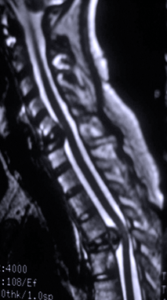

Spinal Cord Tumor and Spinal Tumor Surgery

Spinal tumors involving the spinal column, spinal cord and nerves are uncommon disorders and few centers have experience for these typically complex problems. The most common types of nerve and spinal cord tumors are astrocytomas, ependymomas, schwannomas, and meningiomas. Other tumors involving the spinal column are metastatic tumors, sarcomas, chordomas and an array of rare pathologies.

The treatment of these cases are either involving delicate microsurgery of the nerves and spinal cord or complex reconstruction of the spinal column if there is spinal instability from spinal tumors causing destruction of the spinal column. Some cases will require both microsurgery and reconstruction and Dr Johnson has some of the most experience in the Western US in all aspects of these problems.